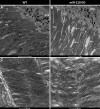

Results: We further investigated lipid anabolism and catabolism in miR-210 knock-out (KO) flies, uncovering significant alterations in gene expression within these pathways. Additionally, we characterized the retinal morphology of flies overexpressing (OE) miR-210, which was not affected by the increased levels of the microRNA. For the first time, we also characterized the retinal morphology of miR-210 KO and OE mice. Similar to flies, miR-210 OE did not affect retinal homeostasis, whereas miR-210 KO mice exhibited photoreceptor degeneration. To explore other potential parallels between miR-210 KO models in flies and mice, we examined lipid metabolism, circadian behaviour, and retinal transcriptome in mice, but found no similarities. Specifically, RNA-seq confirmed the lack of involvement of lipid metabolism in the mice's pathological phenotype, revealing that the differentially expressed genes were predominantly associated with chloride channel activity and extracellular matrix homeostasis. Simultaneously, transcriptome analysis of miR-210 KO fly brains indicated that the observed alterations extend beyond the eye and may be linked to neuronal deficiencies in signal detection and transduction.